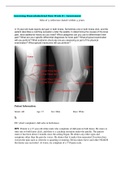

Assessing Musculoskeletal Pain Week 8 | Assessment

A 15-year-old male reports dull pain in both knees. Sometimes one or both knees click, and the patient describes a catching sensation under the patella. In determining the causes of the knee pain, what additional history do you need? What categories can you use to differentiate knee pain? What are your specific differential diagnoses for knee pain? What physical examination will you perform? What anatomic structures are you assessing as part of...